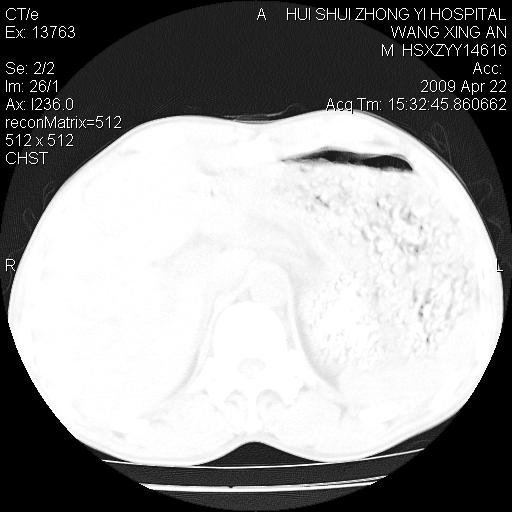

1、右下肺中央型肺癌并右肺转移,右肺中下叶不张。(右肺有结节影)。胸骨转移

2、右中上肺陈旧性肺结核(因为大多为纤维灶)。

3、右侧胸腔积液。